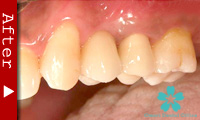

数本の歯を失った場合

この場合もインプラントが理想的な解決法となります。数本のインプラントを歯のない部分に入れ、これを土台としてヘッド部にブリッジをかぶせます。